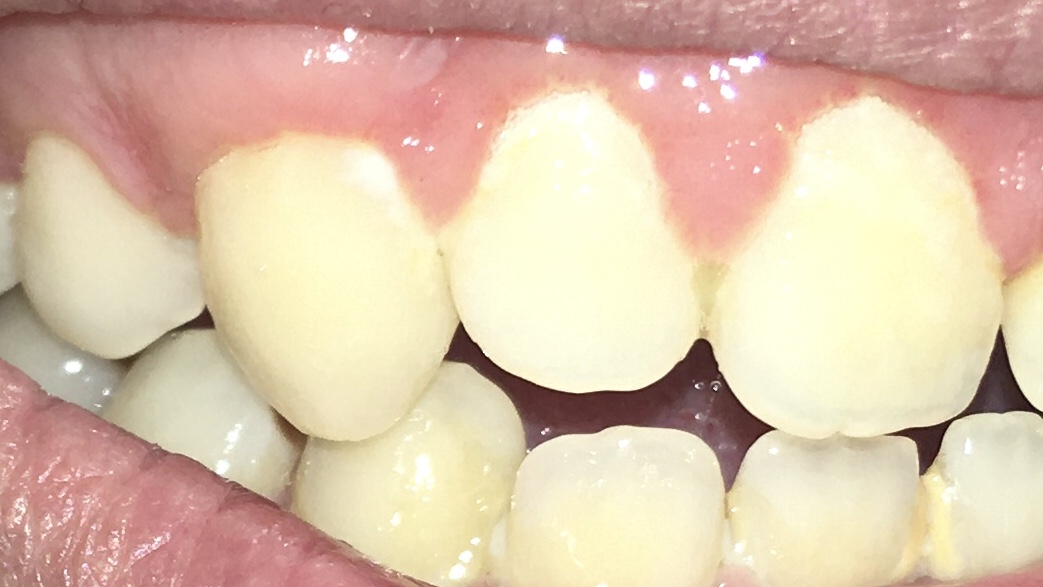

Опустились дёсны в нескольких местах, обнажились шейки зубов. Чувствительные, болят от прикосновений, могут реагировать на холодное, горячее, сладкое.

А чем такое как у тебя, оп, отличается от кленовидного деффекта?

клиновидный это повреждение шейки, рецессия убыль десны.